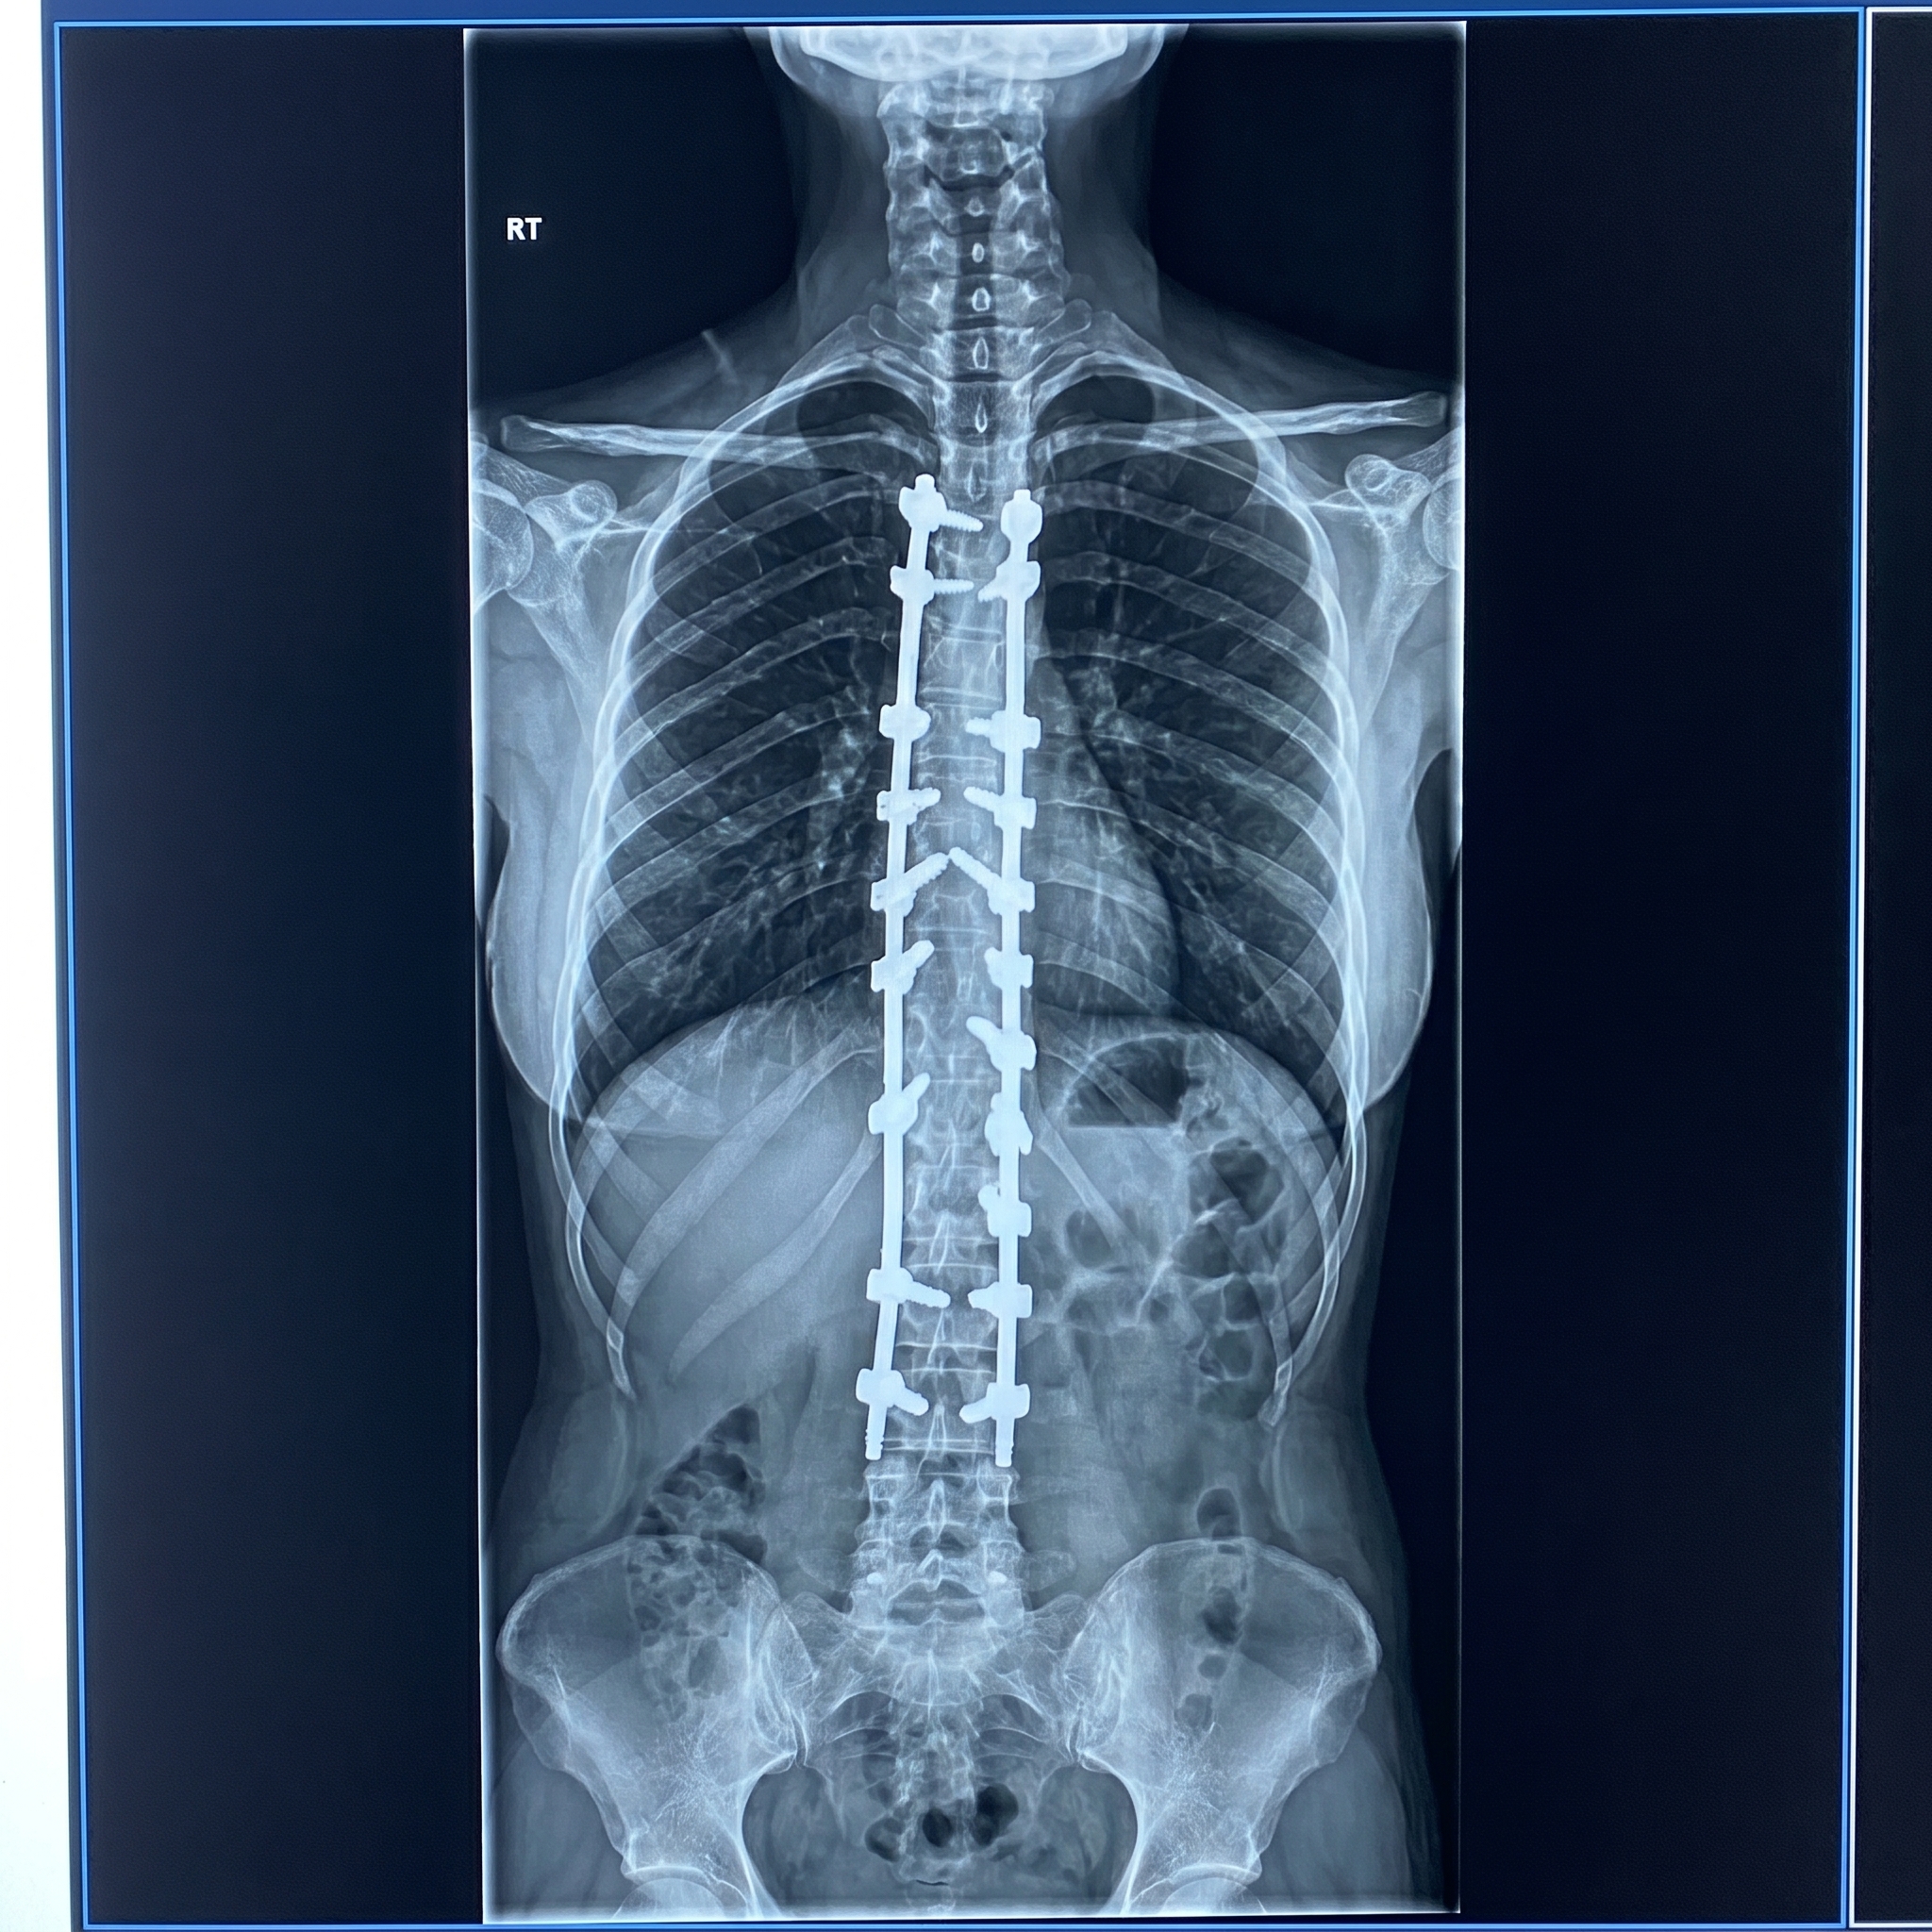

طولت ٥ سم مرة واحدة بعد تعديل تقوس الظهر ..و رغم الام الشد على عضلات الظهر نتيجة فرق الطول الا انها كانت بتتمشى عادي تاني يوم العملية

ركبنا ١٩ مسمار و كسرنا و عدلنا ظهرها المقوس المتيبس بزاوية تعدت ال ٩٠ درجة و رجعناه للشكل الطبيعي.

دا فيديو بيحكي تجربة سيده ٣٧ عام تعاني من #تقوس_مهمل بالعمود الفقري منذ الطفولة ازداد مع الوقت حتى تعدى ال ٩٠ درجة و تم تعديله بنجاح .. في الام اختفت و باقي فقط الام عضلات الظهر اللي اتمطت اكتر من ٥ سم بتخف بالتدريج يوم عن التاني.